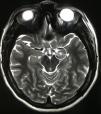

Materiales y métodosSeleccionamos a 8 pacientes pediátricos con TNI bajo un estricto protocolo. Se les realizó electroencefalograma, videoelectroencefalograma y resonancia magnética previo a la cirugía. El síntoma neuroagresivo irreductible fue tratado con cirugía estereotáctica hacia los blancos cerebrales más descritos para agresividad, y posteriormente evaluado mediante la Overt Agressive Scale en el prequirúrgico y a los 6 meses de seguimiento, usando el test de Wilcoxon para el análisis estadístico.

Materials and methodsEight pediatric patients met strict criteria for IND and were enrolled in this study. Electroencephalography (EEG), video electroencephalography (VEEG) and magnetic resonance imaging (MRI) were performed in all patients prior to surgery. Irreducible neuroagressive symptom was approached by lesional therapy based on most described targets for this disorder and assessed by The Overt Agressive Scale (OAS) pre-operatively and 6 months following surgery, using Wilcoxon test for statistical analysis.